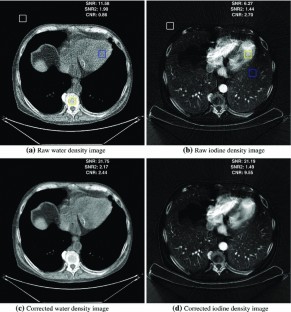

The noise reduction algorithm was applied to a set of images resulting in images with higher SNR and CNR than the raw density images obtained by the decomposition process. The average improvement in terms of SNR gain was about 49 % while CNR gain was about 52 %. The difference between the raw and filtered regions of interest mean values was far from reaching statistical significance (minimum \(p> 0.89\), average \(p> 0.97\)).